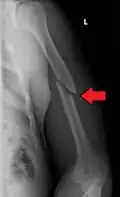

| Midshaft humerus fracture with callus formation | |

A transverse fracture of the humerus shaft -